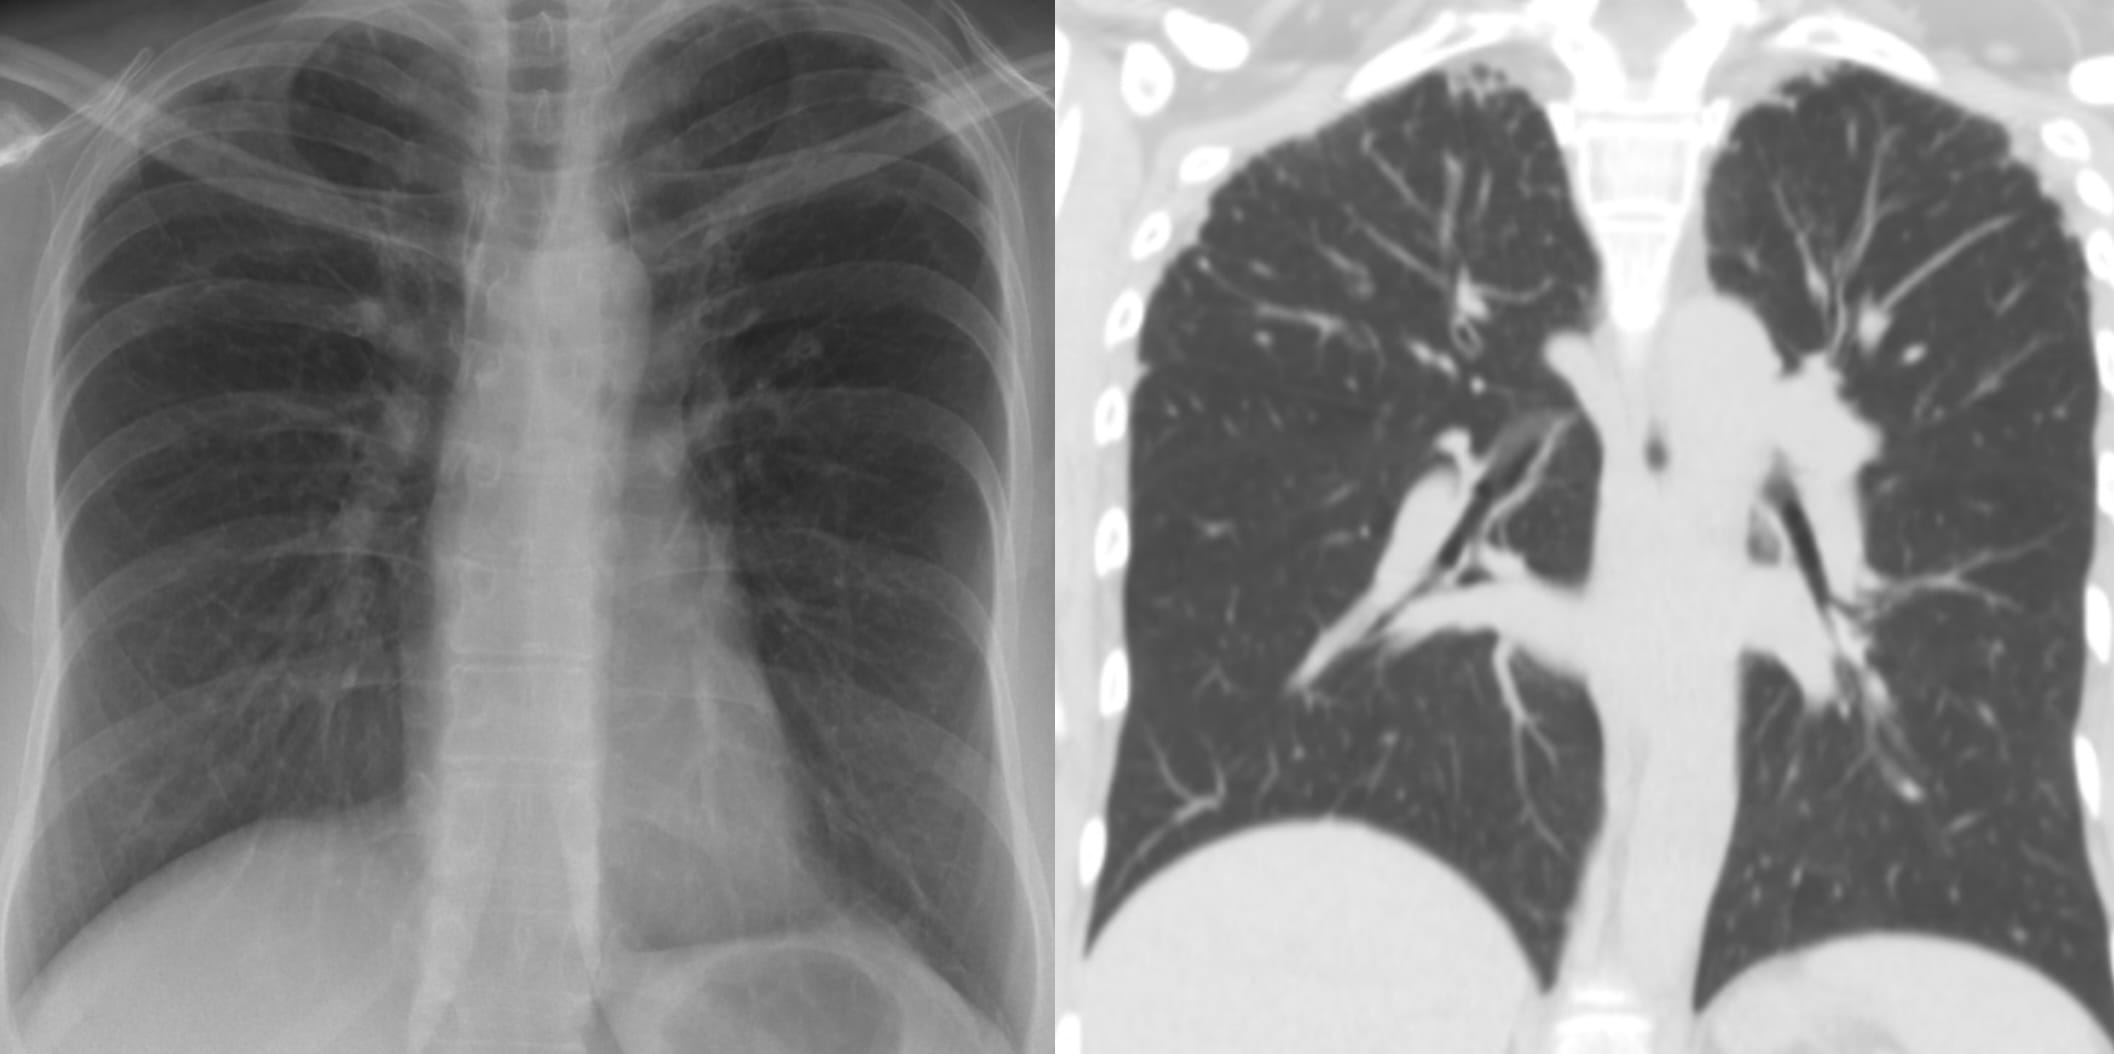

- Usual Interstitial Pneumonia